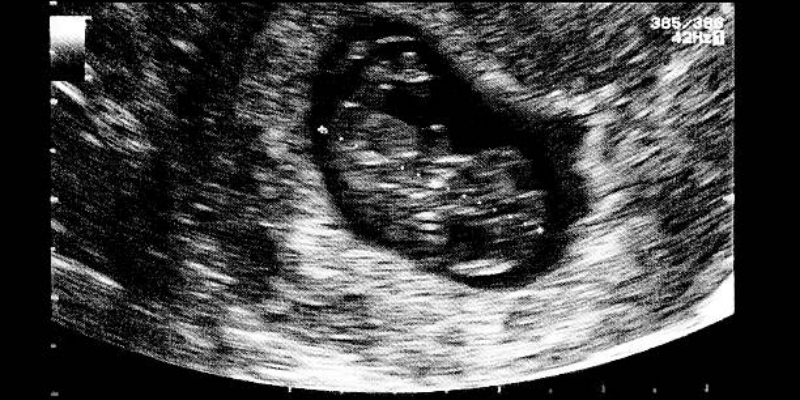

Pada usia kehamilan 7 minggu, janin berukuran sekitar 1,25 cm atau sebesar biji blueberry. Bentuk tubuhnya mulai lebih menyerupai manusia, meski kepala masih tampak besar dibandingkan tubuh. Calon tangan dan kaki juga sudah muncul dalam bentuk tonjolan kecil. Lengan dan kaki mulai bertumbuh memanjang, dan selaput tipis berkembang yang kelak akan menjadi jari-jari mungil.